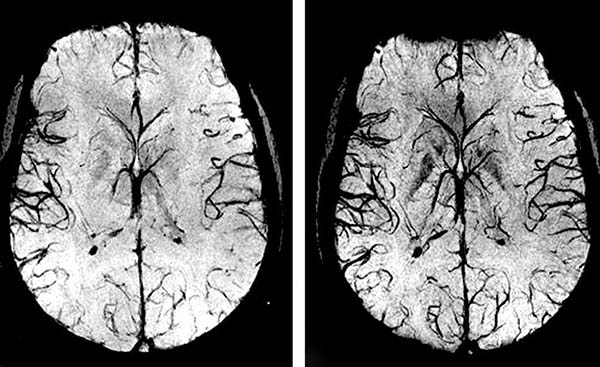

Zaburzone napięcie naczyniowe i normalne krążenie krwi w tkankach mózgu może doprowadzić do angiodystonii naczyń mózgowych.

Angiodystonia naczyń mózgowych – wpływa na pracę całego organizmu. Z powodu niewystarczającego dopływu krwi do mózgu, ogólna wydajność spada, pojawia się osłabienie i ważne układy organizmu zaczynają działać nieprawidłowo. Początkowe objawy obrzęku naczynioruchowego mózgu obejmują m.in. ból głowy; szum w uszach, drętwienie kończyn, osłabienie, zaburzenia snu: zbytnią senność lub problemy z bezsennością.

Aby krew lepiej krążyła w naczyniach mózgowych, należy oczyszczać naczynia całego organizmu z nagromadzonych zanieczyszczeń: płytki cholesterolu, skrzepy krwi i wapno wapniowe.

Pogorszenie krążenia krwi w mózgu rozwija się często w sposób niezauważony przez kilka lat i może zakończyć się udarem.

Jakie jest ryzyko ignorowania objawów zanieczyszczenia naczyń krwionośnych? Choroby będą postępowały, a im więcej zanieczyszczeń zgromadzi się w naczyniach, tym poważniejsze będą konsekwencje. Przy umiarkowanym lub znacznym zanieczyszczeniu naczyń mózgowych najczęściej dochodzi do udaru mózgu i całkowitego lub częściowego paraliżu.